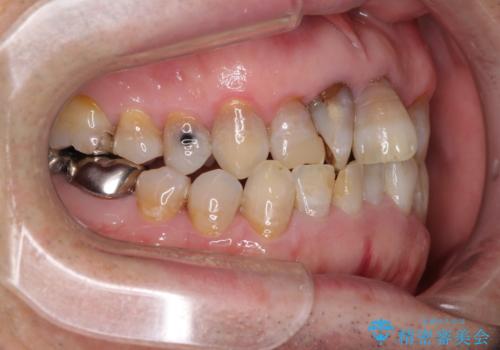

上顎の狭窄歯列 インビザラインによる拡大矯正

- 前歯の叢生と臼歯のクロスバイトを気にして来院された患者様です。

急速拡大装置による上顎の側方拡大を行い、その後はインビザラインより歯列を改善することとしました。

20代後半以降の男性は上顎骨の側方拡大処置の成功率が低く、今回も骨を拡大することができませんでした。

しかしながら、歯列を側方に拡大することができ、その後はインビザラインにて叢生を解消することができました。